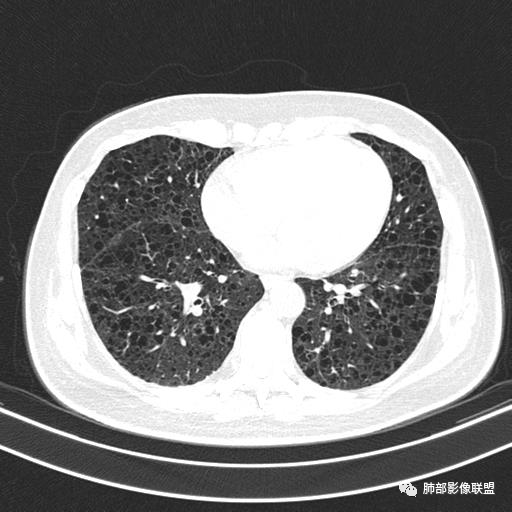

双肺弥漫囊腔,累及肋膈角,囊腔形态相对规则单一。

CT平扫示双肺弥漫分布大小不等囊状薄壁透光区,无内、中、外带分布差异,间质稍示增厚。拟LAM

中年女性育龄期妇女,咳嗽气喘,无吸烟史,有苯吸入史。影像:双肺弥漫均匀小囊腔,无明显分布优势,囊腔形态欠规则,壁薄,部分囊腔边缘血管征,伴双肺弥漫磨玻璃影,无结节,考虑lam,鉴别苯中毒肺损伤,囊腔多有分布优势,小叶中心分布为主,形态规整等

CT表现:双肺弥漫大小不等的薄壁囊腔,囊壁<2mm,外形规则,血管影多位于囊腔周围,囊腔之间肺组织正常,随着疾病进展到晚期,囊腔变大、增多,不可胜数,囊腔可融合成较大的囊,与肺气肿相似,形成间质性肺纤维化。部分病例可出现结节影。